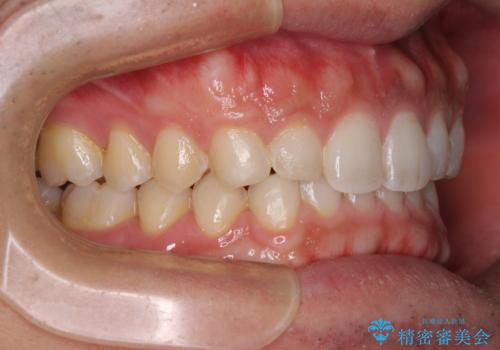

細かい隙間にものがはさまる インビザラインによる矯正治療

- 上下の前歯の隙間を気にして来院された患者様です。

インビザラインを用い、上下歯列のスペースを閉じていくこととしました。

銀行にお勤めのため、突然の転勤により通院が大変な状況となりましたが、インビザラインであれば2-3ヶ月に1度を目安に来院いただき、無事に治療を終えることができました。